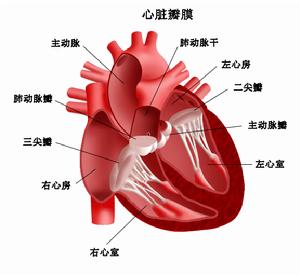

心衰 (二)根據心衰發生的部位可分為左心、右心和全心衰竭。左心衰竭的特徵是肺循環淤血;右心衰竭以體循環淤血為主要表現。

心衰的臨床表現與何側心室或心房受累有密切關係。左心衰竭的臨床特點主要是由於左心房和(或)右心室衰竭引起肺瘀血、肺水腫;而右心衰竭的臨床特點是由於右心房和(或)右心室衰竭引起體循環靜脈瘀血和水鈉瀦留。在發生左心衰竭後,右心也常相繼發生功能損害,最終導致全心衰竭。出現右心衰竭時,左心衰竭症狀可有所減輕。

(六)心臟體徵 主要為原有心臟病表現,由於右心衰竭常繼發於左心衰竭,因而左、右心均可擴大。右心室擴大引起三尖瓣關閉不全時,在三尖瓣聽診可聽到吹風性收縮期雜音。由左心衰竭引起的肺淤血症狀和肺動脈瓣區第二心音亢進,可因右心衰竭的出現而減輕。